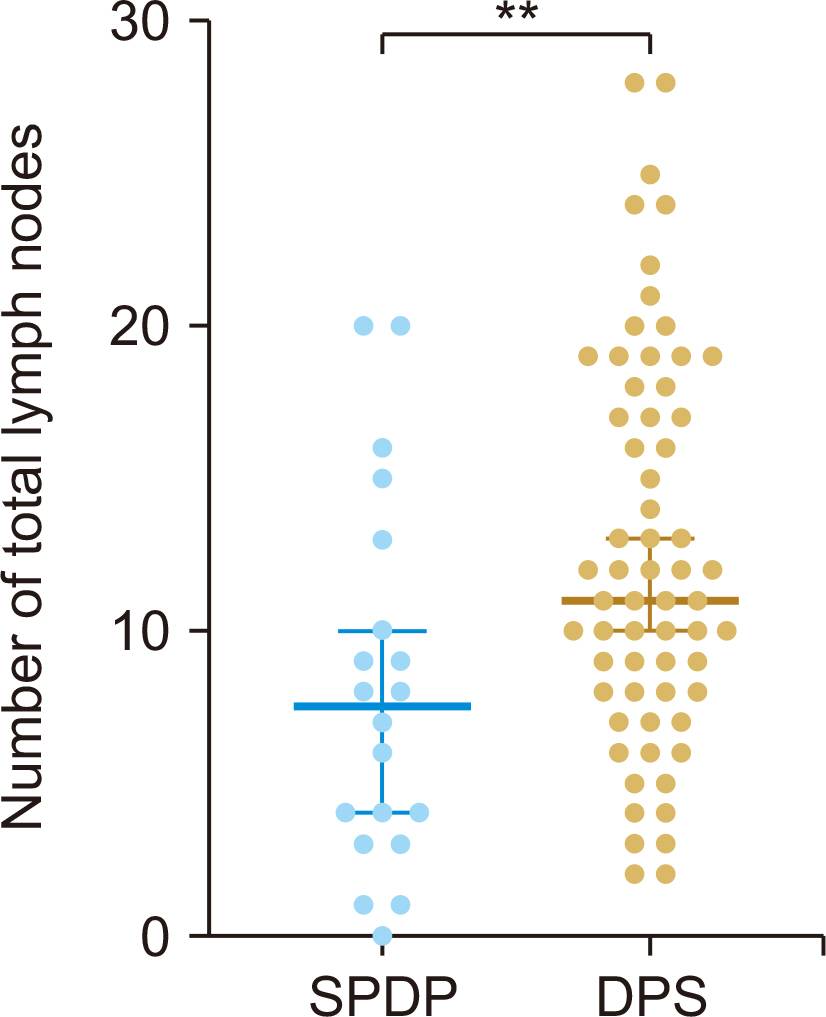

Both groups exhibited similar demographic, intraoperative, and pathological characteristics, with the exception of a reduced number of total lymph nodes (p = 0.006) in the SPDP group. There were no significant differences in the rates of postoperative complications, recurrence, or metastasis. Local recurrence predominantly occurred in the central region as opposed to the spleen region. There were no cases of isolated recurrences in the splenic region. Median overall survival and recurrence-free survival times were 51.5 months for SPDP vs 30.5 months for DPS and 18.7 months vs 16.8 months, respectively (p > 0.05). The incidence of partial splenic infarction and left-side portal hypertension in the SPDP group was 28.6% (6/21) and 9.5% (2/21), respectively, without necessitating splenic abscess puncture, splenectomy, or causing bleeding from perigastric varices.